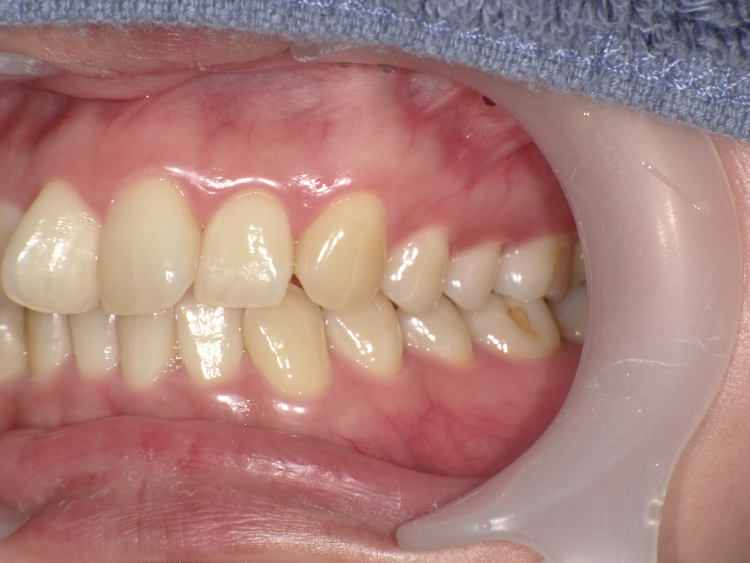

症例5

治療前

治療後

| 主訴 | 右上1番下げたい 1.1間隙間うめたい 上のみ部分矯正希望 |

|---|---|

| 治療 期間 |

約7ヶ月 |

| 治療費 | 175,000円(税込)/調整費用別途 |

| 治療 内容 |

上の前歯部にワイヤーを着けて進めていく、プチ矯正で施術。 |

| 治療の リスク |

奥歯を動かさないので前に出して並べていく。 歯を動かすことで、歯茎が下がるリスクある。 装置による清掃の難しさから、歯肉炎や歯周病、虫歯のリスクが高まる。 矯正終了後は、リテーナーを使用し、後戻りを防ぐ必要がある。 |